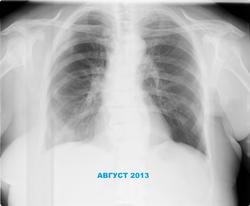

Насчет возрастных - шутка, да? Очаги в левой верхушке, левый корень полез, справа что-то с ребрами. Боковые? Левая молочная удалена, или просто сплющилась?

необычное положение корня левого легкого. Смещение вверх может быть обусловлено: 1. циррозом, но его не видно, 2. резекцией легкого, но не нет танталовых скрепок, однако современные шовные материалы могут быть не видны (вспомним демонстрацию Петровича с удаленной верхней долей правого легкого); 3. ателектазом сегментов верхней доли. В остальном, согласен с Алексеем Станиславовичем.

"Смещение" левого корня может быть обусловлено кифосколиозом,а вот справа в верхнем поле что-то:то ли действительно с ребрами,то ли плевральные наслоения,то ли еще чего.Насчет добавочноой доли,-иногда так выглядят утолщенные стенки сегментарных бронхов у пожилых людей,но это не важно в данном случае.А вот левой молочной железы не видно.Может анамнез,да и жалобы какие-нибудь есть?

Думаю там целый комплекс причин, ведущими из которых является фиброз в верхней доле (постлучевой) и сколиоз.

Про левосторонюю мастэктомию уже написал, что была в 2011г.

Качательно высокого положения левого корня, соглашусь, что дело в сколиозе и постлучевом фиброзе, как уже написал выше.

P/S: РМЭ слева конец 2011г. ХЛТ.

На верхушке левого легкого постлучевой фиброз.